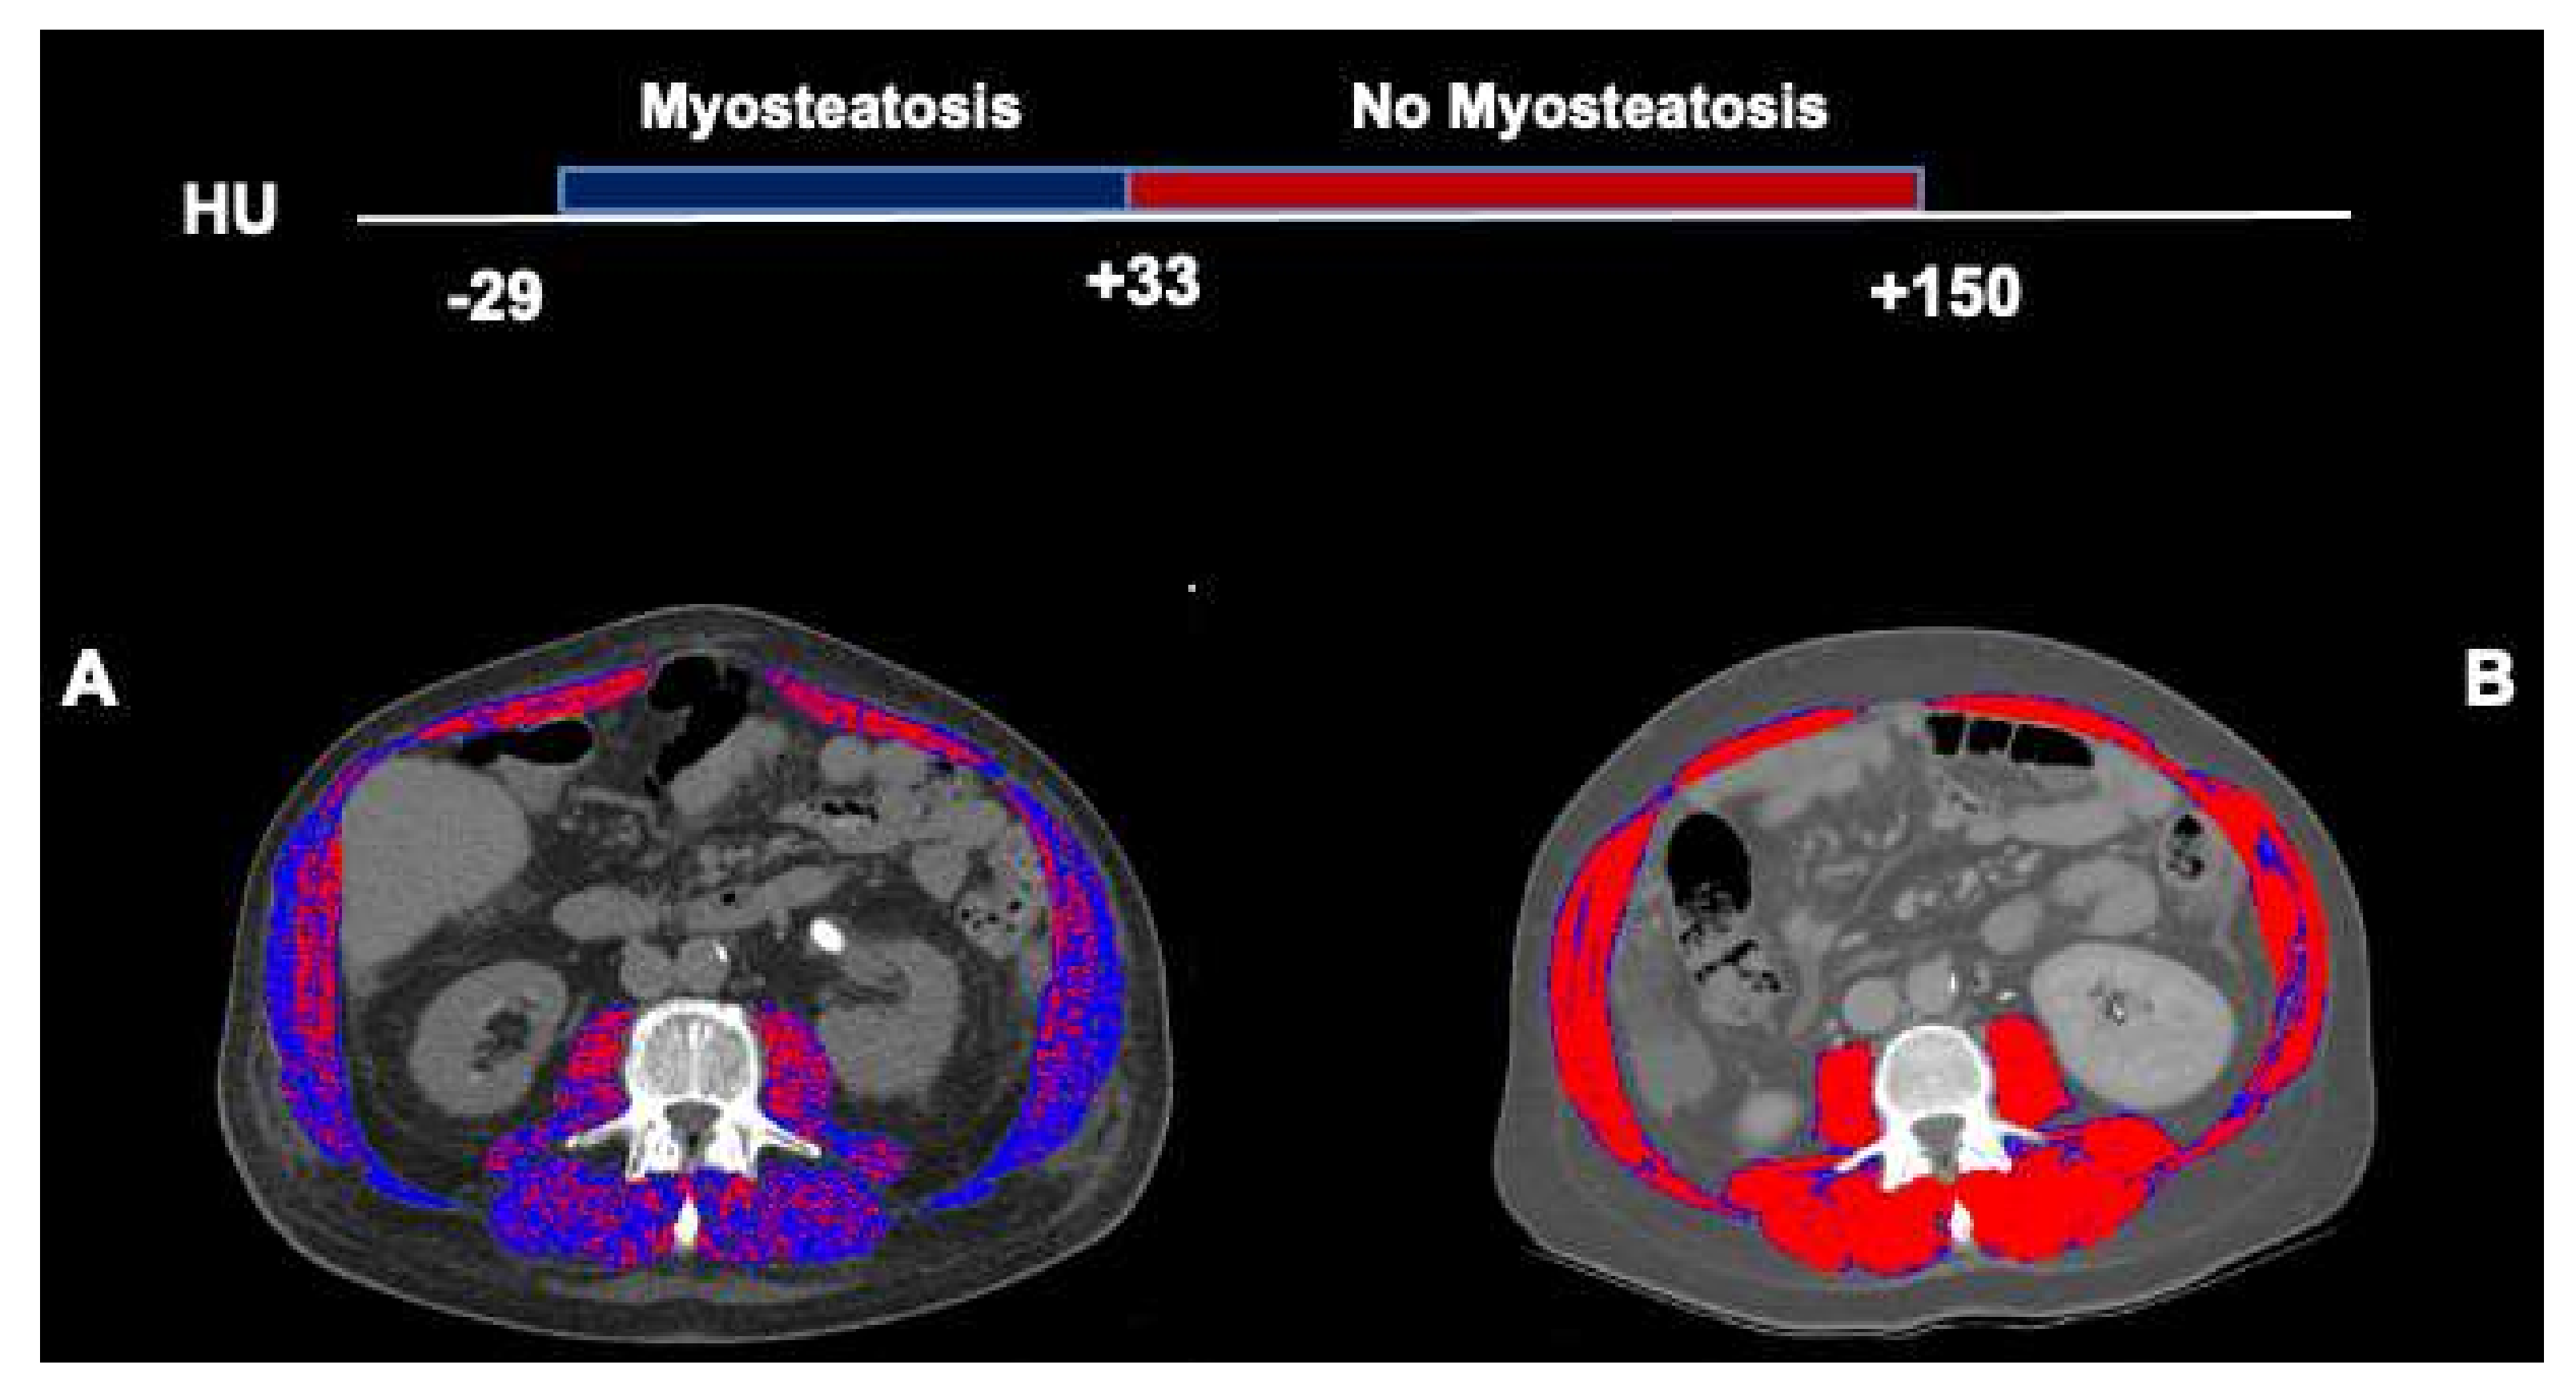

2.2. Computed Tomography Image Analysis